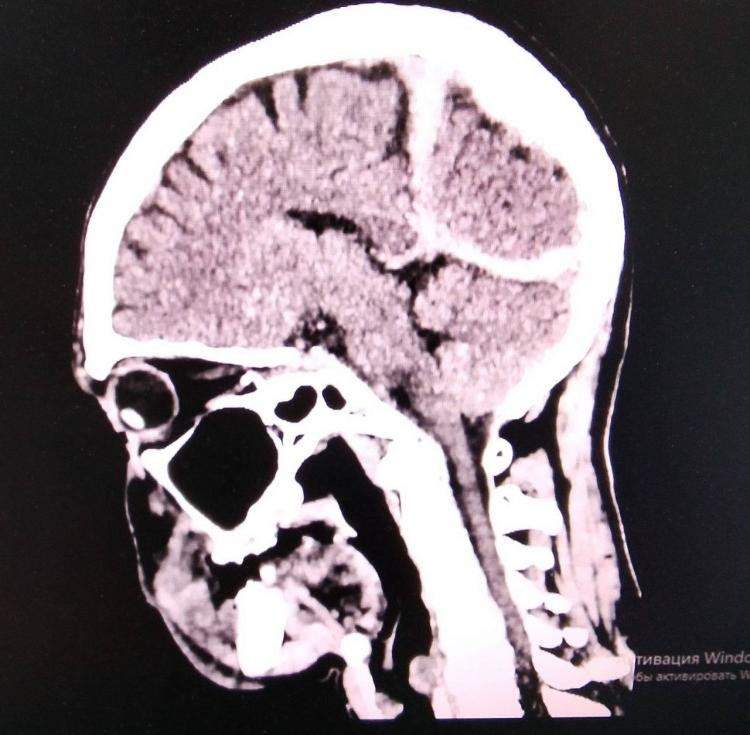

При обследовании врачи выявили у пациента опасный набор травм: субдуральную гематому (скопление крови в тканях мозга), ушиб головного мозга и глубокую рану головы. Все это сопровождалось общим переохлаждением организма. Состояние мужчины оценивалось как критическое.